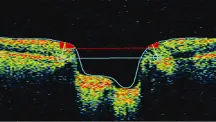

Optical coherence tomography